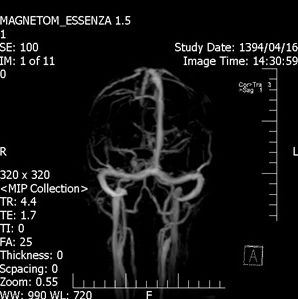

An Occipital Headache as the First Presentation of Multiple Third, Fourth, and Lateral Ventricular Cavernous Malformations: A Case Report and Review of Literature

Background: Cavernous hemangiomas are common benign vascular malformations. Their existence in the intraventricular region is very rare. Case Reports: A 43-year old woman with an occipital headache was admitted to the emergency ward. Brain computed tomography scan showed mild hydrocephalus and multiple intraventricular isodense lesions. Imaging findings, especially of Gradient Resonance Echo imaging, were in favor of multiple intraventricular cavernous malformations. Conclusion: This is a rare presentation of multiple cavernous malformation as occipital headache without needing surgical intervention in this phase. Coexistence of periventricular plaques like Radiologically isolated syndrome of Multiple sclerosis is another unique aspect in this report. [GMJ.2017;6(1):61-65]